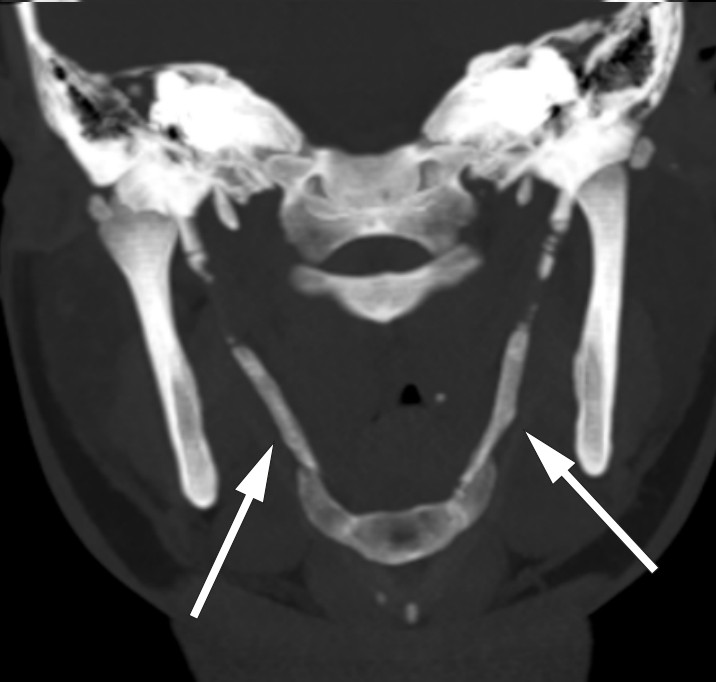

Symptomene ble fremprovosert og forverret med sidebøy og rotasjon av hodet mot høyre. Anamnestisk hadde hun hatt en lignende og forbigående episode to år tidligere. Det var ikke noe hode- eller nakketraume i sykehistorien. Klinisk undersøkelse var upåfallende, foruten palpasjonsømhet peritonsillært og over venstre nakkehalvdel. Omfattende utredning med nevrofysiologiske, bildediagnostiske og øre-nese-hals-undersøkelser viste normale funn. CT-undersøkelse av nakken avdekket forkalkning i ligamentum stylohyoideum bilateralt (se piler), noe som kunne forklare pasientens symptomer.